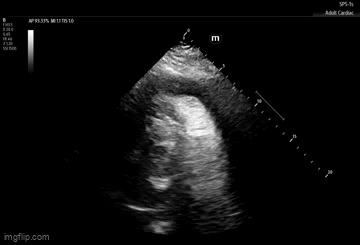

Right Ventricular Diastolic Collapse

You can identify right ventricular diastolic collapse in all 4 cardiac windows, however we suggest starting with the parasternal long and short views to exhibit this finding in at least two views.

Diastole is defined when the mitral valve is open. During right ventricular diastolic collapse, you will appreciate that when the mitral valve is open that the fragile right ventricular wall collapses inward toward the interventricular septum. If you are seeing an associated pericardial effusion, this is highly concerning for tamponade physiology.

Another way to identify RV diastolic collapse is to use M-Mode in the parasternal long view. Place the M-Mode tracing through the RV and mitral valve and run the tracing. When the mitral valve is open (diastole), you can see the RV collapsing on the tracing.